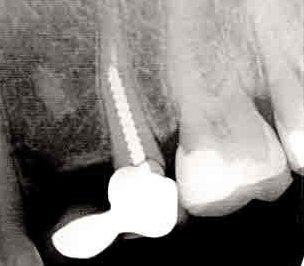

Какво се случва с кореновия канал, ако пълнежът излезе извън него?

Ако пълнежът излезе извън коренови канал, това може да създаде проблеми. Излизането на пълнежа може да доведе до инфекция или реинфекция на зъба. В такъв случай е необходимо да се консултирате със зъболекар, който може да прецени дали е необходимо повторно лечение на кореновите канали или други процедури за спасяване на зъба.